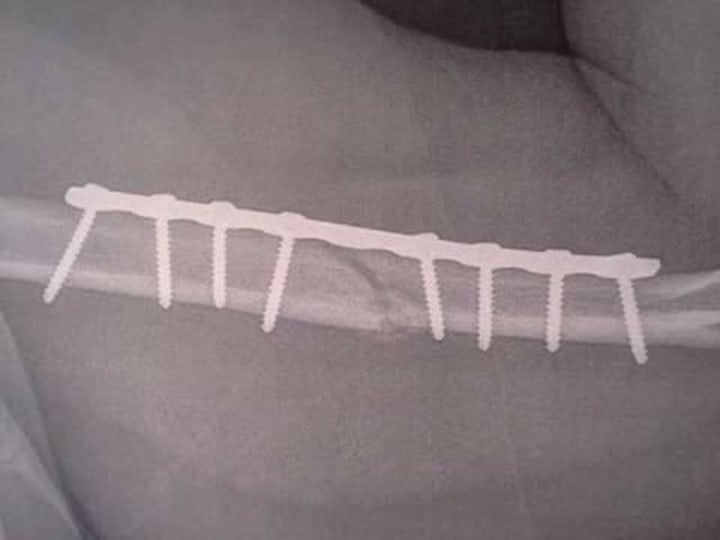

I was put under sedation so they could reset my hip, and splint my arm, and when I woke up, a trauma doctor cleaned and stitched the cuts on my face. I was admitted and ended up having surgery the day after the accident. They wanted to implant a titanium plate onto the bone I broke in my arm to stabilize it (my brother, upon seeing one of the x-rays, said that it looked like my arm had a second elbow. Not good).

1 Titanium Plate and 8 Screws later. Plus one hell of a gnarly scar on my arm.